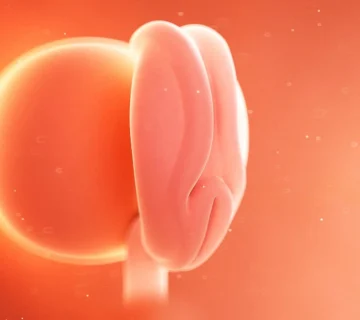

رشد سیستم عصبی و ماهیچهها

در این مرحله، بدن او شروع به ساخت مایلین (Myelin) میکند؛ مادهای چرب که مانند روکش از رشتههای عصبی محافظت میکند و انتقال پیامهای عصبی بین مغز و سایر اندامها را سرعت میدهد. جالب است بدانید در همین زمان، تعداد رشتههای عصبی جنین تقریباً برابر با یک انسان بالغ است!